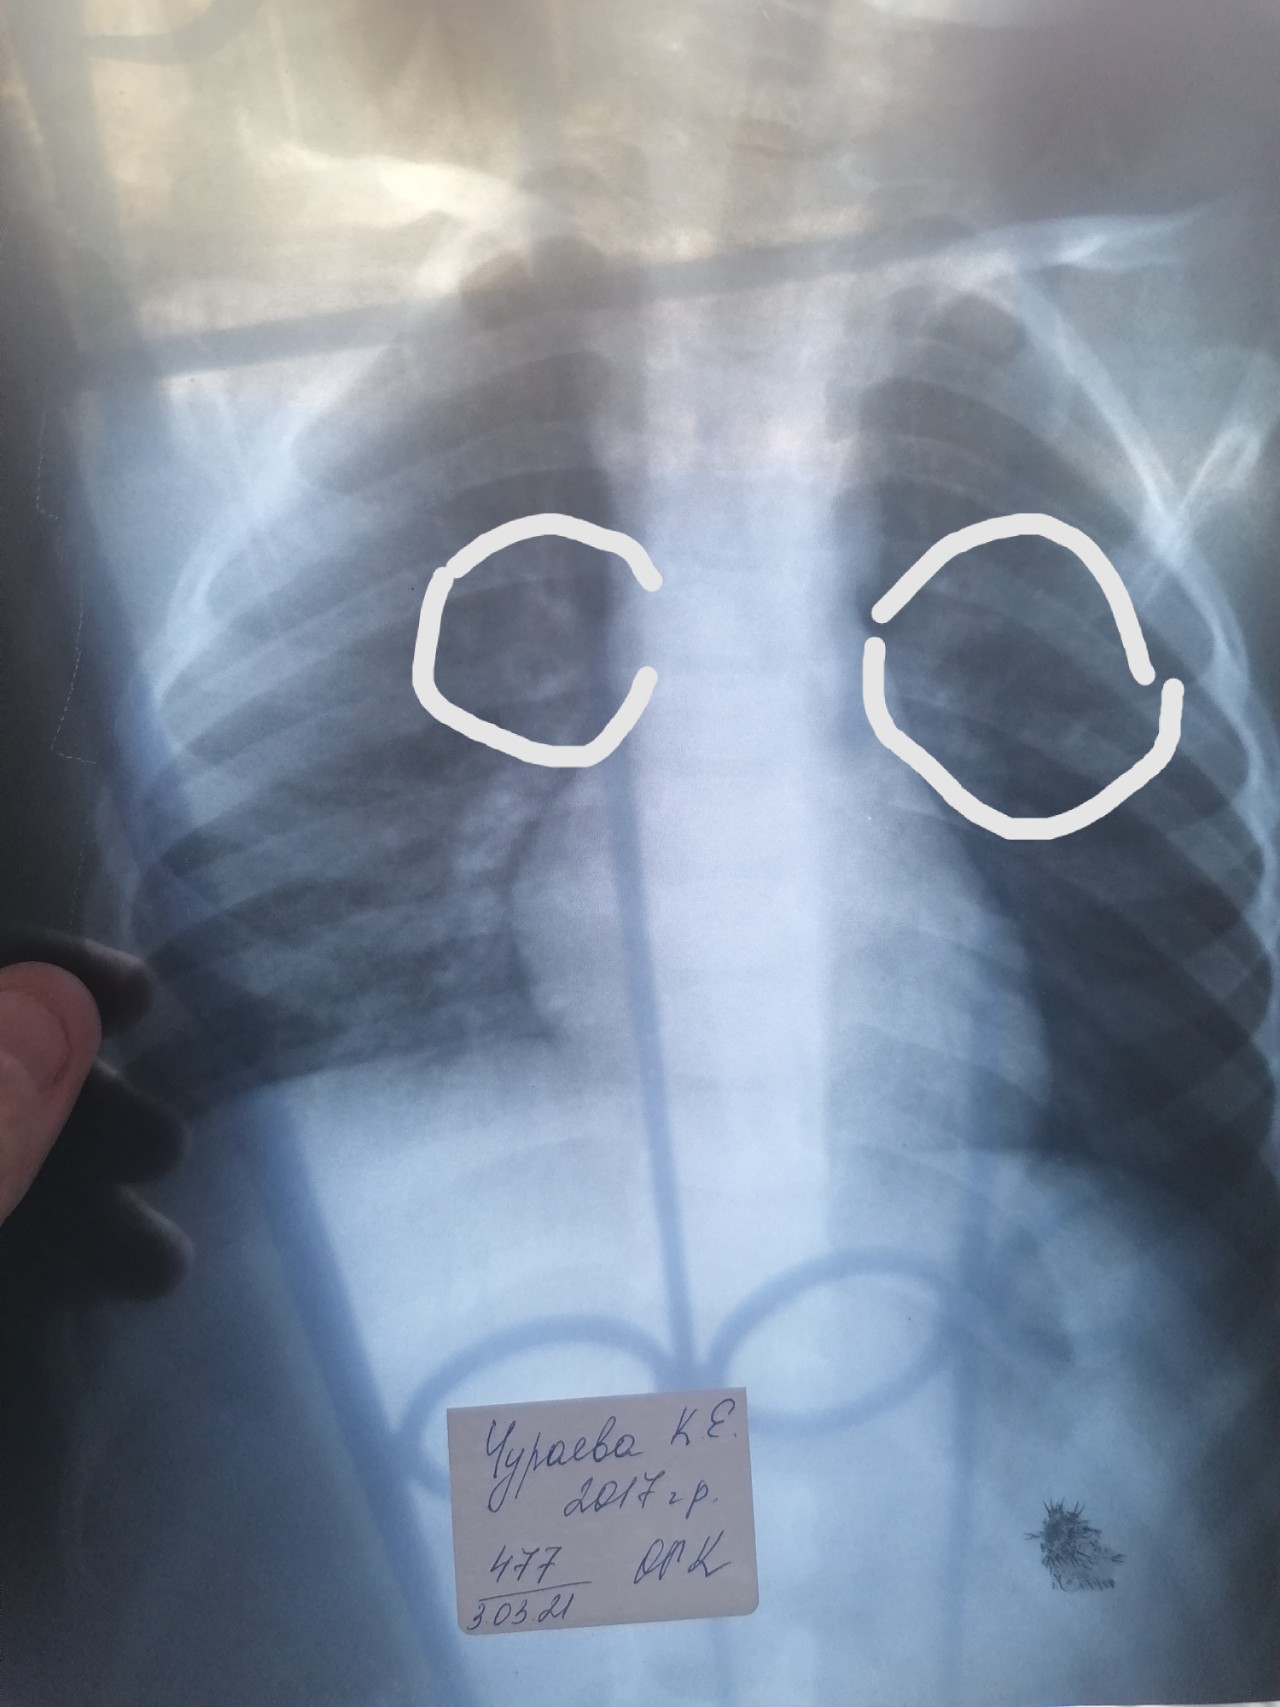

Креативные рентген-снимки рук с изображением сердечка

Раздел: Необычные решения